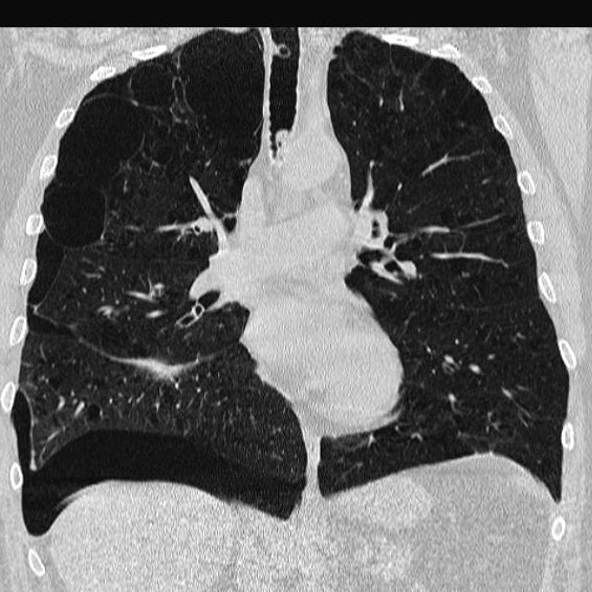

Même das en

coupe coronal . Le pneumothorax est presence du

poumon droit de apex à longitudinal peripherique du

poumon et se presence dans espace sus dipragmatique

droit . Le poumon droit est collabe legerement .